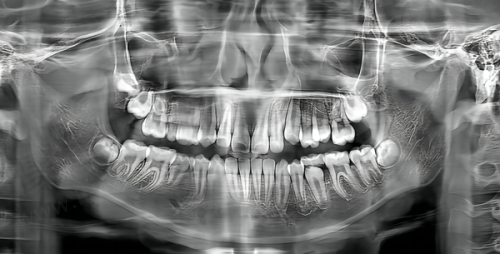

3. 诊疗服务:江宁总院每天的营业时间是09:00 - 18:00。这里能提供洗牙、补牙、种植牙、牙齿矫正等多项口腔医疗服务。作为主院区,设备那是相当齐全,医生团队实力也特别强,不管多复杂的口腔问题,他们都有办法解决。比如说,在种植牙方面,医院配备了CBCT三维影像系统、口扫仪等精良设备,能支持精细诊断与个性化方案设计。通过3D打印技术定制种植导板,还能降低手术风险呢。